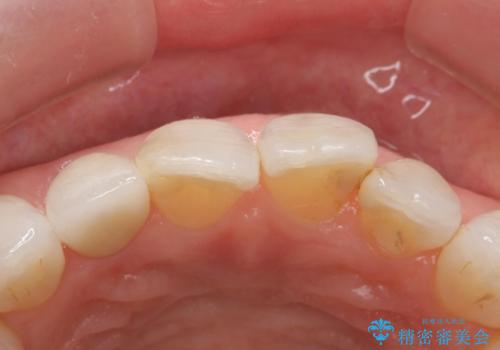

他の歯との調和のとれたクラウンを装着することができ大変喜んでいただけました。

- 右上2 仮歯/11,000円 ファイバーコア/22,000円 ジルコニアクラウン(スペシャル)/154,000円 合計187,000円費用は治療当時の料金となります